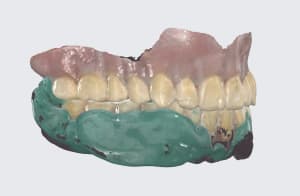

Capture d’écran 2026-03-21 à 20.02.00.png